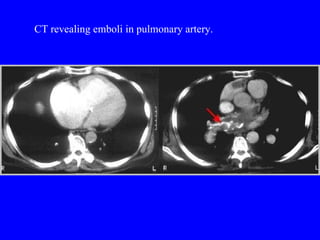

CT revealing emboli in pulmonary artery.

CT revealing emboliin pulmonary artery.